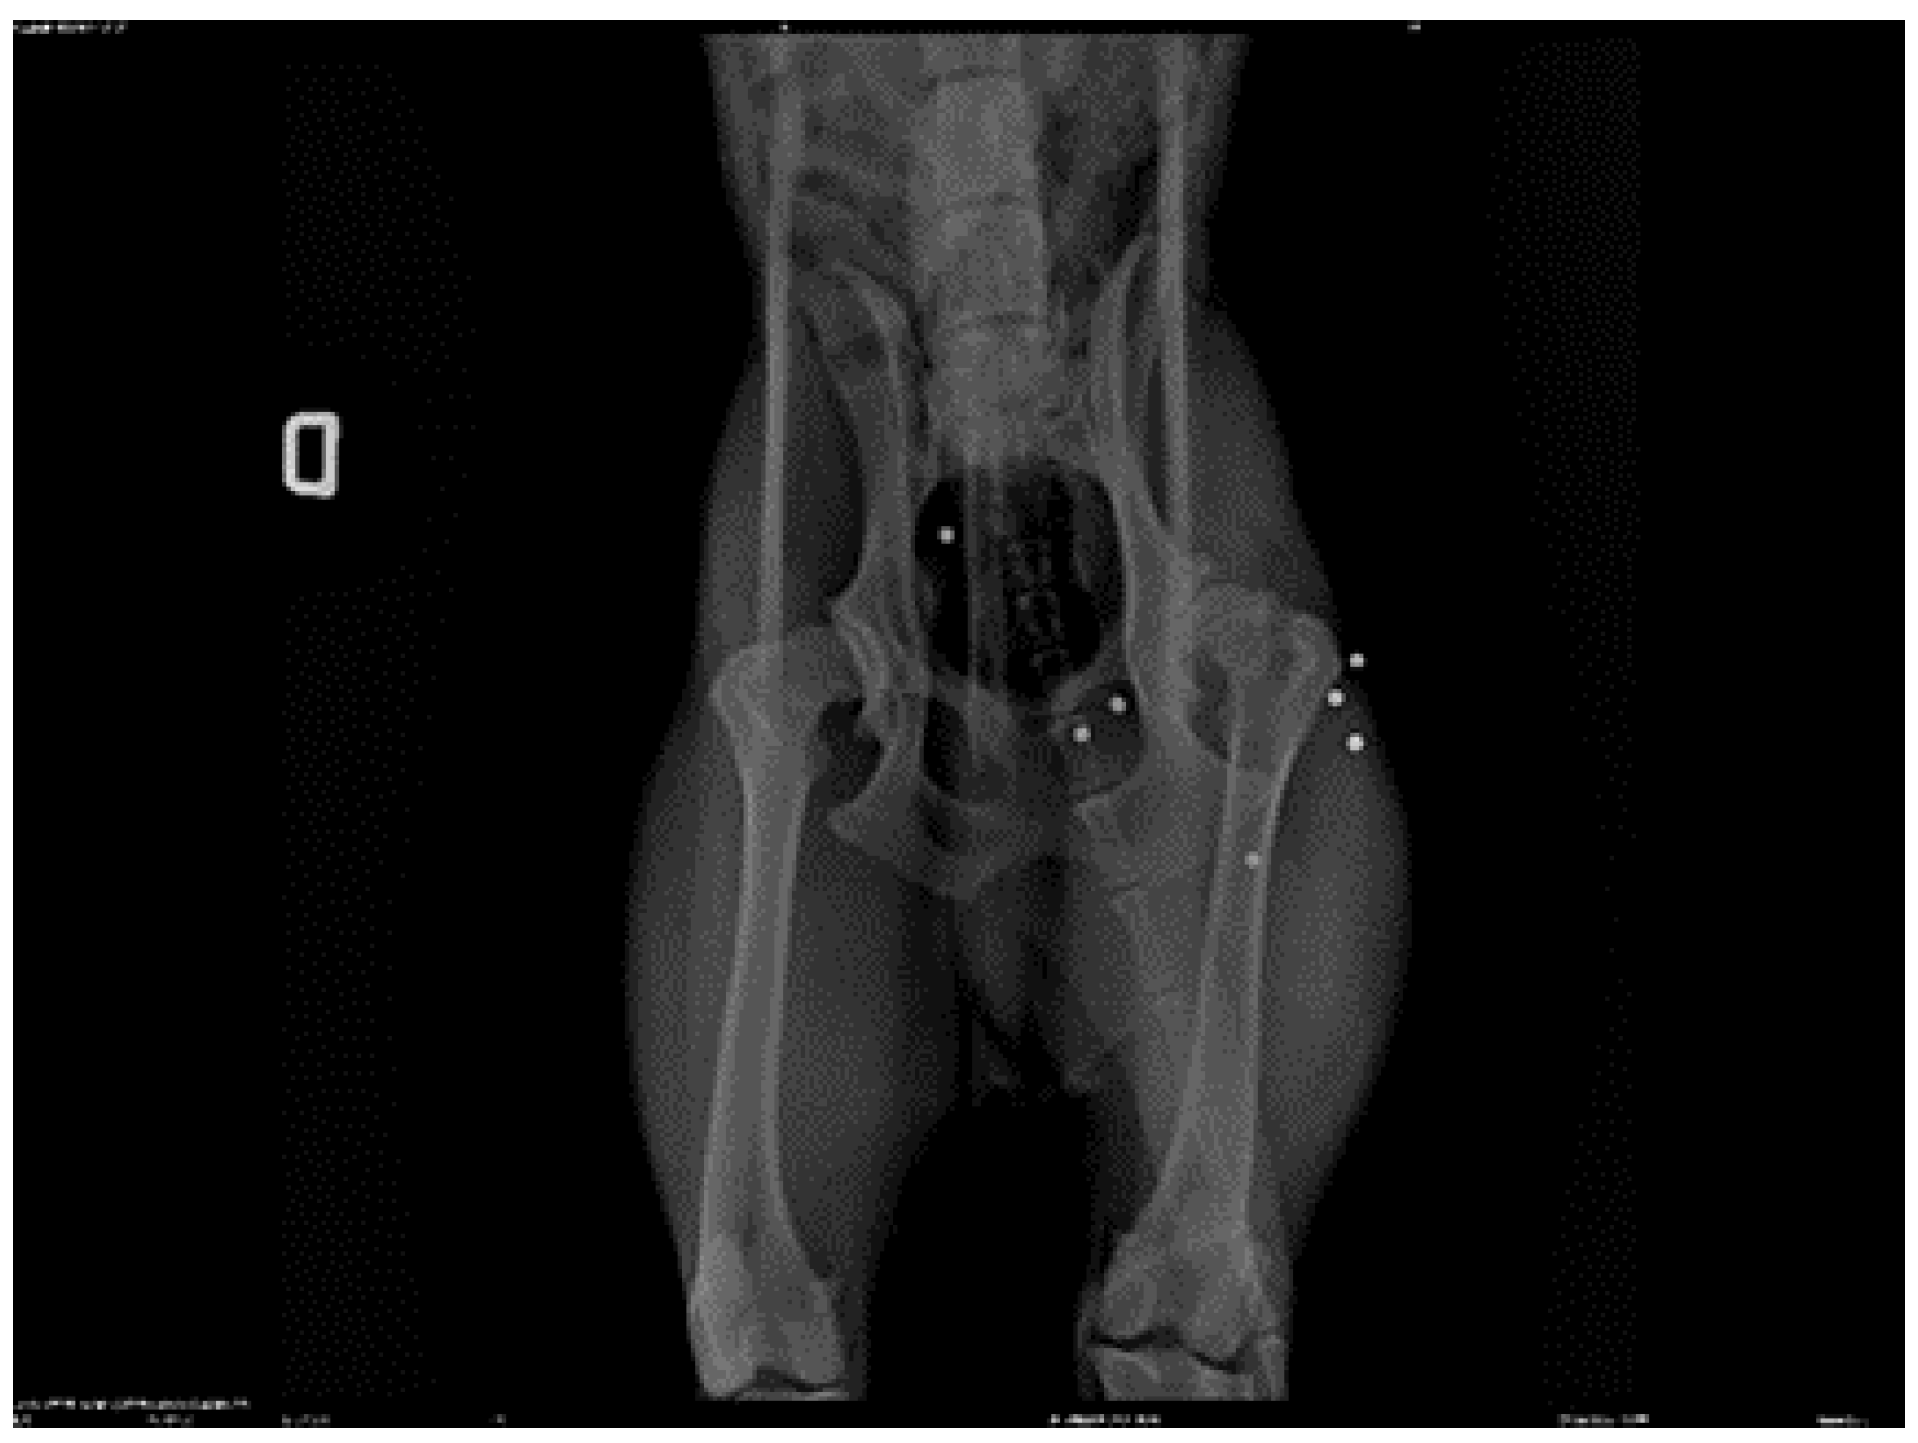

![]() |